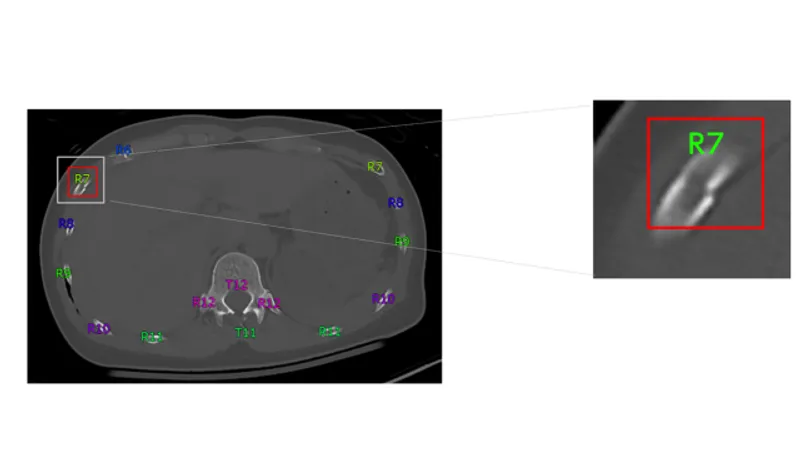

胸部CT画像から肋骨骨折の候補を検出して表示する機能です。医師が再確認することで見落しを低減します。

本プログラムは、胸部CT画像をオンプレ/クラウド環境にて自動解析し、肋骨骨折が疑われる箇所を検出してマーキングするソフトウェアです。

CT画像から三次元解析する当社技術を活用することで、骨表面を構成する皮質骨の断裂が認められる箇所を肋骨骨折の候補として検出します。また、SYNAPSE SAI viewer*1に搭載されている、医師が骨折の場所などを指し示す際に引用する「骨番号」を自動付与する「ラベリング機能*2」を併用でき、所見文を作成する際の負荷を軽減します。さらに、二次元画像から三次元画像を構成して観察できる 「VR機能」と併用すると、どの方向から外傷を受けたのかなど、骨折の原因分析に活用できる三次元的な情報を確認することができます。 *1 SYNAPSE SAI viewer用 画像表示プログラム 販売名:画像診断ワークステーション用プログラム FS-V686型 認証番号:231ABBZX00028000 *2SYNAPSE SAI viewer用 画像処理プログラム 販売名:画像診断処理プログラム FS-AI683型 認証番号:231ABBZX00029000